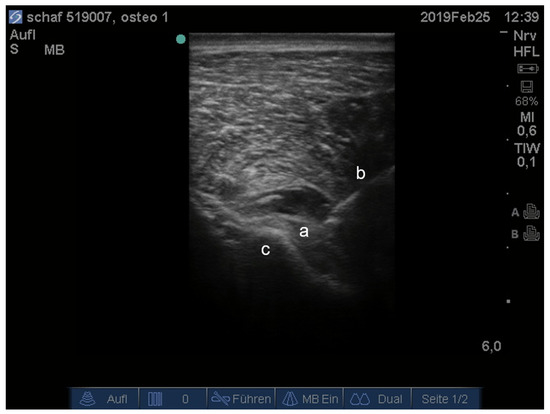

- Waag, S.; Stoffel, M.H.; Spadavecchia, C.; Eichenberger, U.; Rohrbach, H. Ultrasound-guided block of sciatic and femoral nerves: An anatomical study. Lab. Anim. 2014, 48, 97–104. [Google Scholar] [CrossRef]